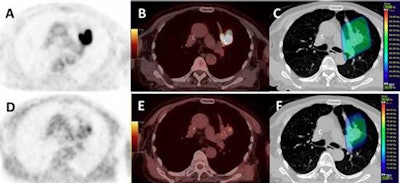

All patients underwent two FDG-PET/CT and two FMISO-PET/CT scans on the same scanner and under identical conditions. In 24 (70%) of 34 patients who had positive FMISO results, the radiotherapy dose was increased up to 86 Gy on hypoxic areas identified on FMISO-PET/CT. However, this additional dose did not improve patient outcomes (JNM, July 2017, Vol. 58:7, pp. 1045-1053).

At the three-month follow-up, 31 patients (57%) showed a favorable response to the radiotherapy, including 17 (50%) of the 34 patients in the FMISO-positive group. At one year, overall survival was 63%, and disease-free survival was significantly longer among patients whose FMISO scans were negative (p = 0.004). Radiotherapy dose, however, was not associated with disease-free survival when adjusted for patients' FMISO status.